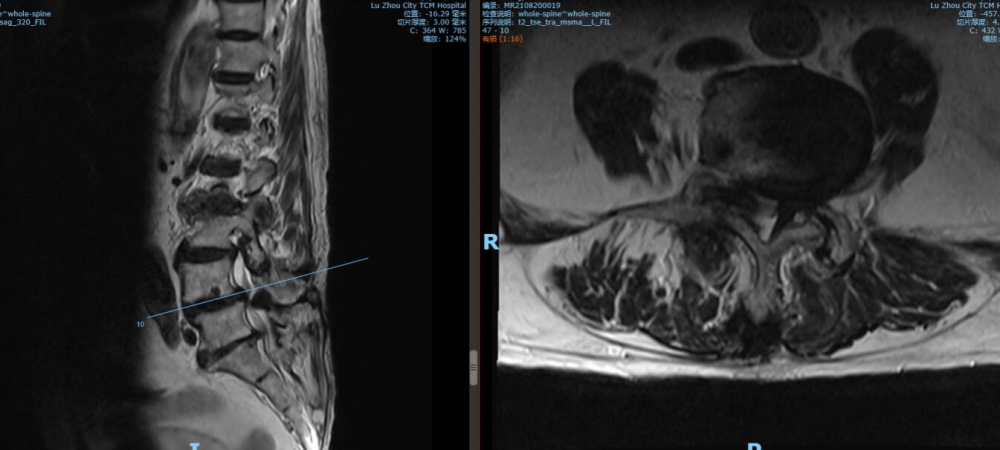

4 5椎間盤CT

4 5椎間盤MRI